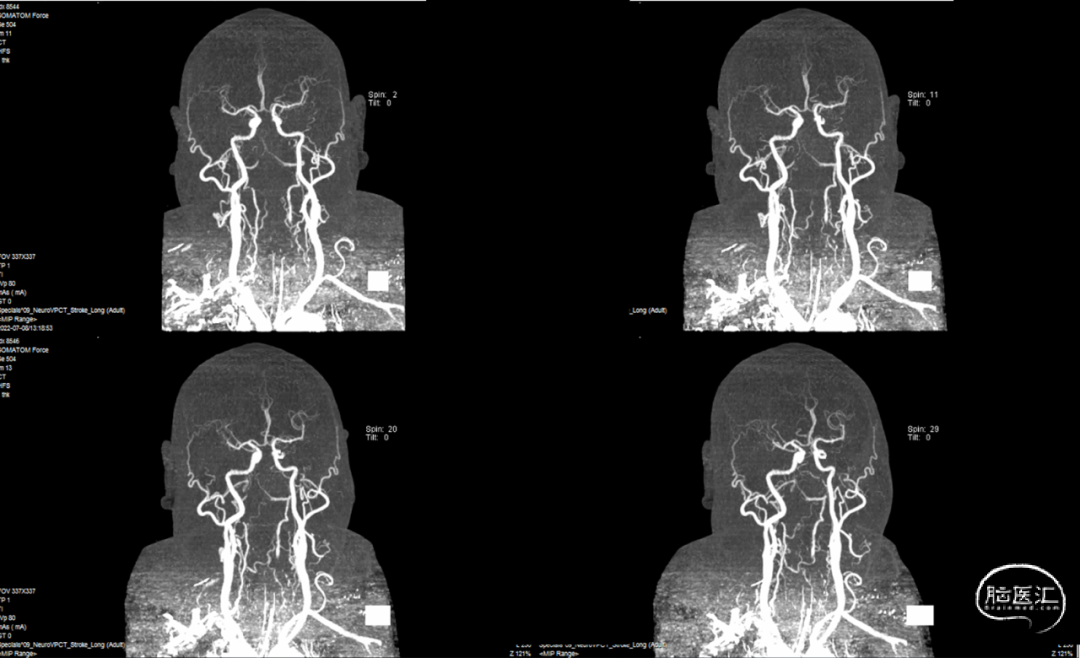

综合术前辅助检查,(Core+pen)/Core=3.58;Pen>15ml;Core<70ml(图3);发病时间小于24小时,存在取栓指征,但是当地医院手术经验告诉我们左侧椎动脉慢性闭塞,且开通异常困难,常规手术方案很难成行,术前制定合理且可行的手术方案至关重要。方案1:仍采用左侧椎动脉+基底动脉取栓的正向开通方案,可能会继续浪费大量时间,甚至最后以失败告终。方案2:采用右侧椎动脉入路,由于右侧椎动脉V4段发育不良,当地医院已尝试过超选,证实无法通过V4段至基底动脉建立取栓通路。方案3:既往有文献报道开颅椎动脉直视下穿刺取栓,虽然方案可行,但我院无类似手术经验,贸然尝试风险难以把控。方案4:回顾当地医院取栓影像资料,发现双侧颈内动脉后交通呈胚胎型,是否可能通过后交通跨循环逆向超选至基底动脉取栓。患者平卧DSA床,全麻插管成功后,用碘伏常规消毒手术区皮肤,铺无菌巾单。取双侧股动脉为穿刺点,于14时00分seldinger法穿刺成功后分别置入8F穿刺鞘和5F 短鞘。行全脑血管造影显示左侧椎动脉起始部闭塞,颈升动脉通过肌支代偿V2及以远的椎动脉血流,右侧椎动脉V4段发育不良,单纯供应右侧PICA,双侧后交通动脉胚胎型。(图9,图10)首先我们仍尝试传统入路进行超选左侧椎动脉,发现左侧椎动脉开口闭塞,斑块质地坚硬,微导丝微导管无法通过。短暂尝试无果后,迅速改为右侧椎动脉入路,发现将微导丝塑型成“J”型或成袢,均无法到达右侧椎动脉V4段,遂果断决定采用跨循环取栓方案。将5F VERT造影导管超选至左侧锁骨下动脉,进行正向血流监测。6F 90cm长鞘(cook)及5F 125cm Navien导管在泥鳅导丝带领下超选进入右侧颈内动脉岩骨段。随后将Rebar18微导管在Synchro2微导丝带领下超选至大脑中动脉,并将Navien带领至右侧颈内动脉交通段。微导丝微导管回撤至颈内动脉,路图下Synchro2微导丝带领Rebar18逐步通过右侧后交通动脉,再在透视下经右侧大脑后动脉P1段盲超选至基底动脉下段。(图11-13)手推造影确认Rebar18微导管已突破血栓段,并在基底动脉真腔内。(图14)经Rebar18释放一枚solitaire FR支架(4mm×20mm)覆盖血栓段。SWIM技术负压下抽拉支架1次,抽拉过程中时刻注意系统张力,逐步回撤支架同时适度回撤Navien释放张力,以保证Navien贴近后交通开口而不向后交通动脉内继续深入。撤出支架后,Navien原位保持负压约30秒。(图15)造影复查见基底动脉及其分支再通,支架取出少量血栓(图18)。于14时45分达到远端血流mTICI3级,10分钟后复查造影显示血管通畅,于14时55分末次造影见远端血流维持mTICI3级。(图16,17)术中Dynamic CT未见明显术区出血(图19)。遂缝合穿刺点,结束手术。手术顺利,术中病人情况稳定。术末血压115/58mmHg,脉搏70次/分,呼吸12次/分,氧饱和度100%。术毕送重症监护室。图9. 双侧椎动脉造影:左侧椎动脉起始部闭塞,左侧颈升动脉肌支和右侧椎动脉通过脊髓支代偿V2及以远的椎动脉血流;右侧椎动脉V4段发育不良,单纯供应右侧PICA